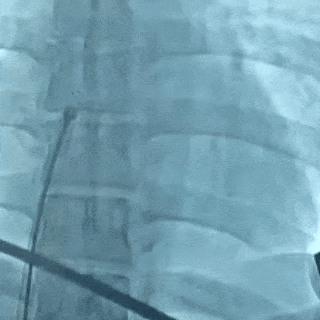

左盘展开

DSA下,左盘面3个Mark点聚拢

封堵器成型,DSA下可见4个Mark点聚拢

锁定后牵拉实验

轻轻牵拉钢缆,4个Mark点依然聚拢在一起

Mark点相对位置未发生变化,并随着钢缆摆动